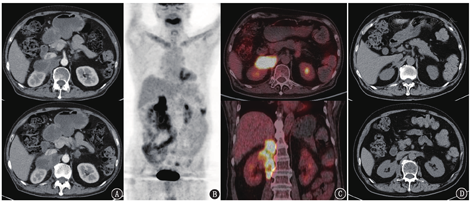

患者2021年9月出现发热、乏力、恶心呕吐、二便失禁,体质量下降约10 kg,血压降低、血钠降低,考虑肾上腺危象,予氢化可的松替代治疗后症状好转(长期方案为早20 mg,晚10 mg)。后续行CT引导下经皮肾上腺占位穿刺活组织检查(左侧),病理见上皮样肉芽肿伴坏死形成,临床考虑为结核感染。患者遂于2021年11月开始行四联抗结核治疗(异烟肼、利福平、乙胺丁醇、吡嗪酰胺);治疗1个月后因出现恶心症状,调整方案:将吡嗪酰胺改为左氧氟沙星,余不变。2022年1月自述恶心加重,暂停利福平和左氧氟沙星,继续口服异烟肼及乙胺丁醇治疗;1个月后症状较前缓解,遂加用左氧氟沙星,维持三联抗结核治疗。2022年6月患者复查腹部增强CT(图5A),结果示双侧肾上腺团块或肿物,增强后呈不均匀强化,其中右侧病变较前明显增大,局部与肝右叶、右肾、右膈脚及下腔静脉分界不清,较大截面约6.2 cm×4.0 cm;左侧病变较前明显变小。

由于右侧肾上腺病变较前明显进展,临床怀疑为恶性病变可能,遂于2022年9月复查18F-FDG PET/CT(图5B、5C),PET/CT示右侧肾上腺见代谢增高的不规则肿物,较治疗前明显增大,并累及右膈脚、右腰大肌,SUVmax 8.8,其中累及腰大肌病灶中央见局部代谢减低区;左侧肾上腺病变较之前明显好转。此时应该如何考虑?之前穿刺活组织检查的是左侧肾上腺病变,抗结核治疗后左侧病变好转,符合肾上腺结核表现。但右侧肾上腺病变明显进展,是否提示右侧是恶性肿瘤?仔细观察右侧肾上腺病灶的特点,发现病变增大主要是呈纵向向下蔓延,有向下流注的趋势,而且病变中坏死区比之前更显著,这些征象很像结核冷脓肿的表现。所以从影像特征来看,考虑右侧肾上腺结核感染较前进展,需要继续规律抗结核或加强治疗,暂不考虑恶性肿瘤。最终临床继续三联抗结核治疗(异烟肼、乙胺丁醇、左氧氟沙星),半年后复查腹部CT见右侧肾上腺病变明显好转(图5D)。